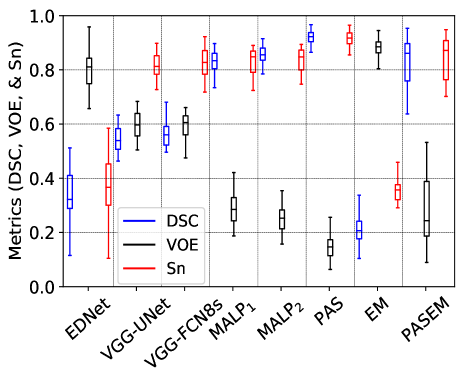

Fig. 7 exhibits the Box and Whisker visualization of all the methods showing the spreads and centers of the DSC, VOE, and Sn metrics for all the 20 test images, either CT or MRI scans.

The experimental results in Table III quantitatively demonstrate that the EDNet is the worst-performing method than the other two CNN-based methods, such as VGG-UNet and VGG-FCN8s, by the margins of and for CT scans and and for MRI scans, respectively, concerning the mDSC. Those two networks also defeat the EDNet for the other two metrics (mVOE and mSn) with significant margins (see in Table III). Although those three networks have the same number of convolutional and pooling layers in the encoder and decoder, they constructionally vary in skip connection employment (see details in subsection II-C). The results on both the imaging modalities reveal that the appliance of skip connection has outputted better-segmented substructures, as the local information from the shallower layers is utilized to reconstruct output masks through the skip connection (see the results in Table III). Again, it is seen from Fig. 7 that the DSC, VOE, and Sn from the EDNet are sparse for both the CT and MRI scans, with significantly fewer median metrics, which demonstrates that EDNet produces scattered results for each of the testing cases. On the other hand, the upper- and lower-whisker for all three metrics are closer for VGG-FCN8s and VGG-UNet than the EDNet (see in Fig. 7), which shows better-robustness of them comparing the EDNet.

Furthermore, the qualitative results in Fig. 8 depict that both the VGG-UNet and VGG-FCN8s provide better-segmented substructures of both the modalities (CT and MRI) than the EDNet. In some examples of the EDNet, none of the target substructures are segmented, which provide VOE as (see upper-whisker in Fig. 7 (b)). The encoders in all three networks have 13-convolutional and 5-pooling layers, where the in-depth features obtained from them have lost spatial location information due to pooling in the encoders. Hence, the output masks from EDNet have less local information, which is solved in the VGG-UNet and VGG-FCN8s due to the concatenation of local information through the skip connection, providing an alternative path for the gradient with backpropagation. It is experimentally validated in our investigations that the additional skipping paths are beneficial for improving the segmentation results of different heart substructures.

Again, it is also remarkable that VGG-FCN8s even exceeds the VGG-UNet (see the corresponding results in Table III, Fig. 7, and Fig. 8) by the margins of and respectively for CT and MRI scans in terms of mDSC. The former network further outperforms the latter network concerning the other two metrics, such as mVOE and mSn, with significant margins for the CT scans. The concatenation of low-level features from the encoder’s antecedent layers with the equivalent decoder scale in VGG-UNet is the possible reason for failing VGG-UNet than VGG-FCN8s [35, 16]. Unessentially, an aggregation of the corresponding scale feature maps from the beginning layer of the encoder, is observed as a weakness of the UNet, as it imposes an undesirable merging procedure, forcing aggregation barely at the corresponding scale feature maps of the encoder and decoder, which was similarly experimentally validated in [35] and our previous article for other medical imaging modality [16]. On the other hand, in VGG-FCN8s, we fuse the feature maps from the encoder’s different coarseness starting from the third block of the encoder, making it a winner of three implemented CNN-based WHS approaches.

III-A2 Results for MALP-based methods

The label propagated segmentation results utilizing different deformed atlas images are quantitatively and qualitatively manifested in Table III, Fig. 7, and Fig. 8. The median and MVF schemes of level propagation, as described in subsection II-B2, generate the heart segmentation results with the mVOEs of and , respectively, for CT scans and and , respectively, for MRI scans. Table III demonstrates that the MVF scheme outperforms the median method of MALP by the margins of and respectively for CT and MRI modalities for mDSC. The former MALP method also outperforms the latter MALP method with significant margins concerning the other two metrics (mVOE and mSn). The Box and Whisker visualization of all three metrics in Fig. 7 for both the methods demonstrate the superiority of the MVF scheme than the median strategy for both the imaging modalities. Fig. 8 (top) and Fig. 8 (bottom) exhibit the qualitative results respectively for CT and MRI scans for both the median (MALP1) and MVF (MALP2) schemes. Those results qualitatively confirm that the segmented substructures from MALP1 suffer from the outliers (see in fifth and sixth columns of Fig. 8), where most of the organs are erroneously labeled with other organs. All the experimental results reveal that the MVF scheme has better dealt with the outliers as it counts the majority of the labels from the voting candidates, whereas the median method estimates the median values of the counter, which may not be matched by the majority voters.

III-A3 Results for probabilistic atlas-based methods

The WHS results of the probabilistic atlas are exhibited in Table III, Fig. 7, and Fig. 8, where we employ our three methods, such as PAS, EM, and PAS+EM (see details in subsection II-B2). The PAS, EM, and PAS+EM schemes of probabilistic atlas provide the heart segmentation results with the mVOEs of , , and , respectively, for CT scans and , , and , respectively, for MRI scans. Table III exhibit that the PAS scheme exceeds the other two methods, such as EM and PAS+EM, by the margins of and for CT scans concerning the mDSC, respectively, whereas it also beats them by the margins of and for MRI scans, respectively, in terms of the mDSC. Similarly, the EM and EM+PAS are also defeated by the proposed PAS method for mVOE and mSn for both the chest imaging modalities with considerable margins (see in Table III). The spreads and centers of the DSC, VOE, and Sn metrics for all the 20 test images (either CT or MRI scans), as exhibited in Fig. 7, also reveal the supremacy of the proposed PAS method over the other two methods (EM and EM+PAS).